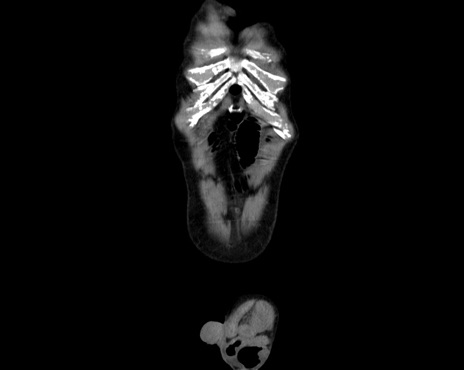

症例26(冠状断像)

【症例】80歳代男性

【主訴】嘔吐

【現病歴】昨晩2回嘔吐あり、今朝になっても嘔吐あり。来院。

【既往歴】胃潰瘍

【身体所見】意識清明、BT 37.6℃、BP 166/95mmHg、HR 100bpm、SpO2 97%、腹部:平坦・軟、腸蠕動音聴取良好、圧痛なし。

【データ】WBC 21900、CRP 1.4